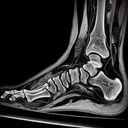

МРТ гомілково-ступневогу суглобу

МРТ (магнітно-резонансна томографія) гомілково-ступневого суглоба – це неінвазивний метод діагностики, який використовує магнітні поля та радіохвилі для отримання детальних зображень м'яких тканин, кісток, зв’язок та сухожиль у цій області. ### Коли призначають МРТ гомілково-ступневого суглоба: 1. **Травми та пошкодження**: Для оцінки стану зв’язок, сухожиль, хрящів і м'язів після травм...